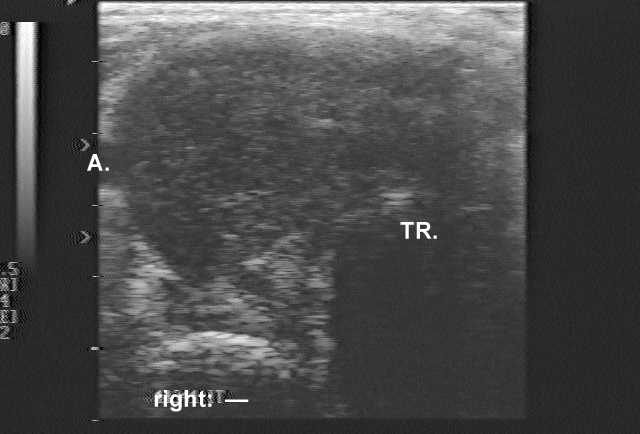

Ultrasonography: demonstrated a greatly enlarged hypoechogenic thyroid spreading retrotracheal and substernal. The vascularization was absent.